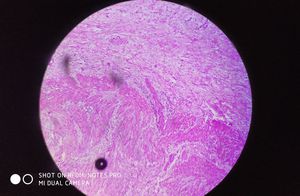

What are this

35yrs old man

Pathology

Histology

Histopathology